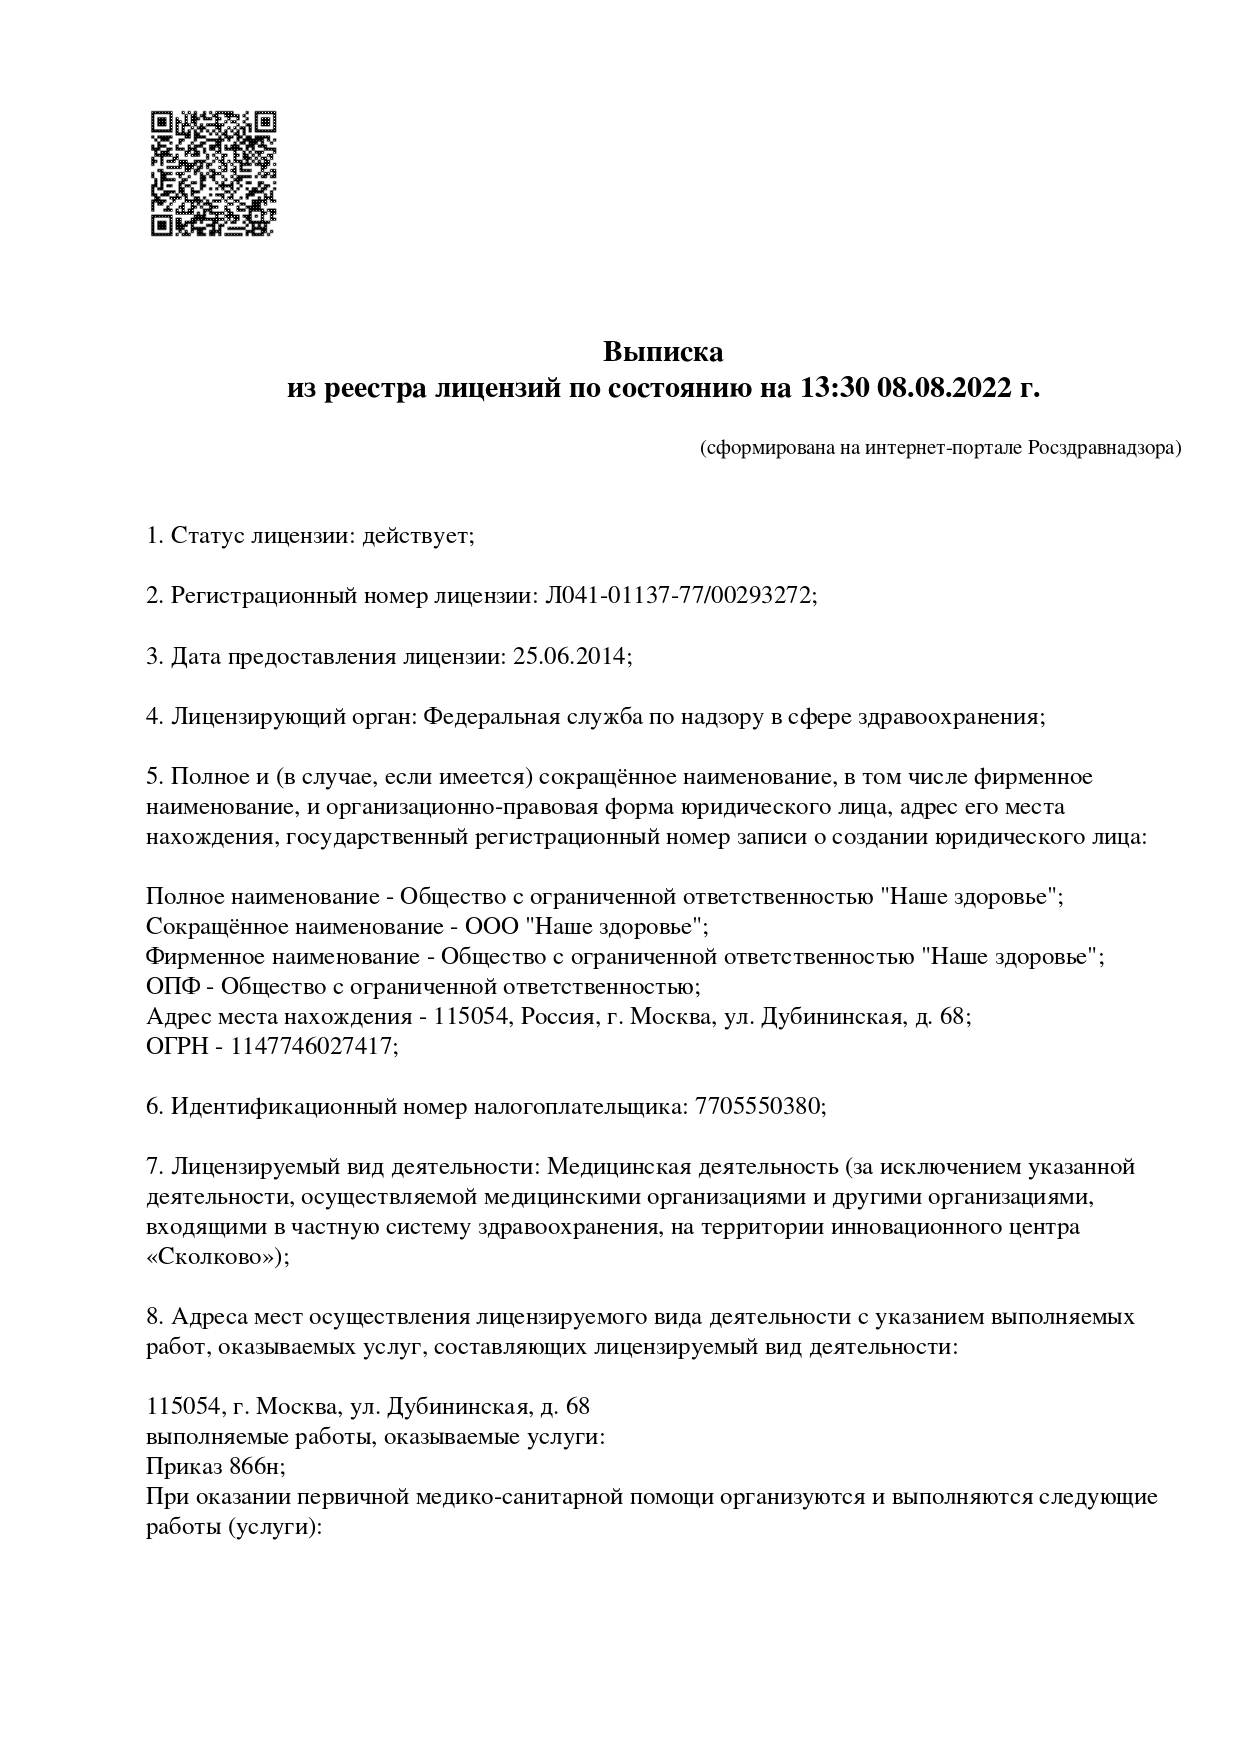

- Лицензии